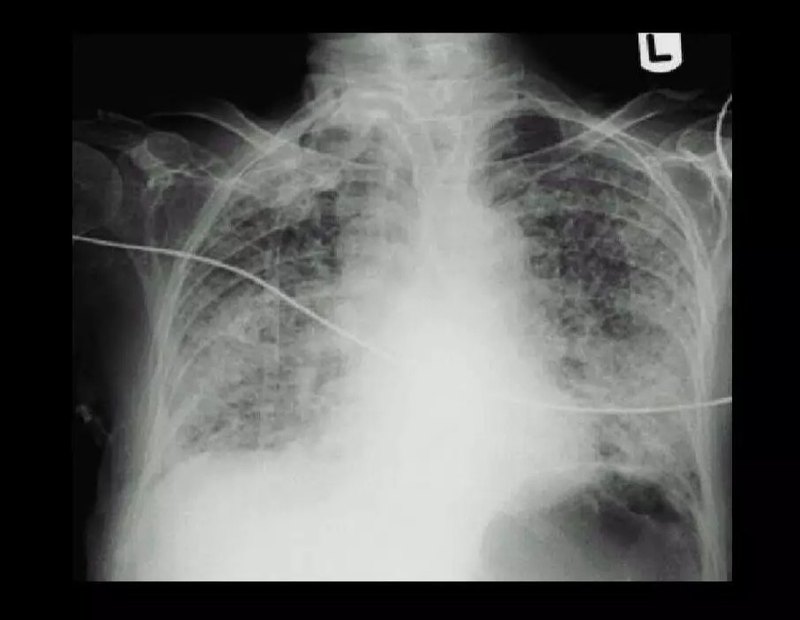

急性呼吸窘迫綜合征(acute respiratory distresssyndrome,ARDS)是指嚴(yán)重感染、創(chuàng)傷、休克等肺內(nèi)外疾病襲擊后出現(xiàn)的以肺泡毛細(xì)血管損傷為主要表現(xiàn)的臨床綜合征,屬于急性肺損傷(acute lung injury,ALI)的嚴(yán)重階段或類型。其臨床特征包括呼吸頻速和窘迫,進(jìn)行性低氧血癥,X線呈現(xiàn)彌漫性肺泡浸潤(rùn)。 治療措施 關(guān)鍵在于原發(fā)病及其病因,如處理好創(chuàng)傷,遲早找到感染灶,針對(duì)病的菌應(yīng)用敏感的抗生素,制止炎癥反應(yīng)進(jìn)一步對(duì)肺的損作; 更緊迫的是要及時(shí)糾正患者嚴(yán)重缺氧,贏得治療基礎(chǔ)疾病的寶貴時(shí)間。

Guidelines for the diagnosis and treatment of acute lung injury / acute respiratory distress syndrome 中華醫(yī)學(xué)會(huì)重癥醫(yī)學(xué)分會(huì)前言急性肺損傷(ALI)/急性呼吸窘迫綜合征(ARDS)是一種常見(jiàn)危重癥,病死率極高,嚴(yán)重威脅重癥患者的生命并影響其生存質(zhì)量。盡管我國(guó)重癥醫(yī)學(xué)已有了長(zhǎng)足發(fā)展,但對(duì)ALI/ARDS的認(rèn)識(shí)和治療狀況尚不容樂(lè)觀。中華醫(yī)學(xué)會(huì)重癥醫(yī)學(xué)分會(huì)以循證醫(yī)學(xué)證據(jù)為基礎(chǔ),采用國(guó)際通用的方法,經(jīng)廣泛征求意見(jiàn)和建議,反復(fù)認(rèn)真討論,達(dá)成關(guān)于成人ALI/ARDS診斷和治療方面的共識(shí),以期對(duì)成人ALI/ARDS診斷和治療進(jìn)行規(guī)范。中華醫(yī)學(xué)會(huì)重癥醫(yī)學(xué)分會(huì)以后還將根據(jù)循證醫(yī)學(xué)證據(jù)的發(fā)展及新的共識(shí)對(duì)ALI/ARDS診斷和治療指南進(jìn)行更新。指南中的推薦意見(jiàn)依據(jù)2001年國(guó)際感染論壇(ISF)提出的Delphi分級(jí)標(biāo)準(zhǔn)(表1)[1]。將指南中涉及的文獻(xiàn)按照研究方法和結(jié)果分成5個(gè)層次,推薦意見(jiàn)的推薦級(jí)別分為A~E級(jí),其中A級(jí)為最高。但需要說(shuō)明的是推薦等級(jí)并不代表特別建議,而只是文獻(xiàn)的支持程度。表1 推薦級(jí)別與研究文獻(xiàn)的分級(jí)推薦級(jí)別A至少有2項(xiàng)I級(jí)研究結(jié)果支持B僅有1項(xiàng)I級(jí)研究結(jié)果支持C僅有II級(jí)研究結(jié)果支持D至少有1項(xiàng)III級(jí)研究結(jié)果支持E僅有IV級(jí)或V級(jí)研究結(jié)果支持研究文獻(xiàn)的分級(jí)I大樣本、隨機(jī)研究,結(jié)論確定,假陽(yáng)性或假陰性錯(cuò)誤的風(fēng)險(xiǎn)較低II小樣本、隨機(jī)研究,結(jié)論不確定,假陽(yáng)性和/或假陰性錯(cuò)誤的風(fēng)險(xiǎn)較高III非隨機(jī),同期對(duì)照研究IV非隨機(jī),歷史對(duì)照研究和專家意見(jiàn)V系列病例報(bào)道,非對(duì)照研究和專家意見(jiàn)一、ALI/ARDS的概念與流行病學(xué)ALI/ARDS是在嚴(yán)重感染、休克、創(chuàng)傷及燒傷等非心源性疾病過(guò)程中,肺毛細(xì)血管內(nèi)皮細(xì)胞和肺泡上皮細(xì)胞損傷造成彌漫性肺間質(zhì)及肺泡水腫,導(dǎo)致的急性低氧性呼吸功能不全或衰竭。以肺容積減少、肺順應(yīng)性降低、嚴(yán)重的通氣/血流比例失調(diào)為病理生理特征,臨床上表現(xiàn)為進(jìn)行性低氧血癥和呼吸窘迫,肺部影像學(xué)上表現(xiàn)為非均一性的滲出性病變 [2]。流行病學(xué)調(diào)查顯示ALI/ARDS是臨床常見(jiàn)危重癥。根據(jù)1994年歐美聯(lián)席會(huì)議提出的ALI/ARDS診斷標(biāo)準(zhǔn)[1],ALI發(fā)病率為每年18/10萬(wàn),ARDS為每年13~23/10萬(wàn)。2005年的研究顯示,ALI/ARDS發(fā)病率分別在每年79/10萬(wàn)和59/10萬(wàn)[3]。提示ALI/ARDS發(fā)病率顯著增高,明顯增加了社會(huì)和經(jīng)濟(jì)負(fù)擔(dān),這甚至可與胸部腫瘤、AIDS、哮喘或心肌梗死等相提并論[4]。多種危險(xiǎn)因素可誘發(fā)ALI/ARDS,主要包括①直接肺損傷因素:嚴(yán)重肺部感染,胃內(nèi)容物吸入,肺挫傷,吸入有毒氣體,淹溺、氧中毒等;②間接肺損傷因素:嚴(yán)重感染,嚴(yán)重的非胸部創(chuàng)傷,急性重癥胰腺炎,大量輸血,體外循環(huán),彌漫性血管內(nèi)凝血等[2]。病因不同,ARDS患病率也明顯不同。嚴(yán)重感染時(shí)ALI/ARDS患病率可高達(dá)25%~50%[5],大量輸血可達(dá)40%,多發(fā)性創(chuàng)傷達(dá)到11%~25%,而嚴(yán)重誤吸時(shí),ARDS患病率也可達(dá)9%~26%[6,7]。同時(shí)存在兩個(gè)或三個(gè)危險(xiǎn)因素時(shí),ALI/ARDS患病率進(jìn)一步升高。另外,危險(xiǎn)因素持續(xù)作用時(shí)間越長(zhǎng),ALI/ARDS的患病率越高,危險(xiǎn)因素持續(xù)24、48及72h時(shí),ARDS患病率分別為76%、85%和93%[8]。雖然不同研究對(duì)ARDS病死率的報(bào)道差異較大,總體來(lái)說(shuō),目前ARDS的病死率仍較高。對(duì)1967~1994年國(guó)際正式發(fā)表的ARDS臨床研究進(jìn)行薈萃分析,3264例ARDS患者的病死率在50%左右[9]。中國(guó)上海市15家成人ICU 2001年3月至2002年3月ARDS病死率也高達(dá)68.5%[10]。不同研究中ARDS的病因構(gòu)成、疾病狀態(tài)和治療條件的不同可能是導(dǎo)致ARDS病死率不同的主要原因。二、ALI/ARDS病理生理與發(fā)病機(jī)制ALI/ARDS的基本病理生理改變是肺泡上皮和肺毛細(xì)血管內(nèi)皮通透性增加所致的非心源性肺水腫。由于肺泡水腫、肺泡塌陷導(dǎo)致嚴(yán)重通氣/血流比例失調(diào),特別是肺內(nèi)分流明顯增加,從而產(chǎn)生嚴(yán)重的低氧血癥。肺血管痙攣和肺微小血栓形成引發(fā)肺動(dòng)脈高壓。ARDS早期的特征性表現(xiàn)為肺毛細(xì)血管內(nèi)皮細(xì)胞與肺泡上皮細(xì)胞屏障的通透性增高,肺泡與肺間質(zhì)內(nèi)積聚大量的水腫液[11],其中富含蛋白及以中性粒細(xì)胞為主的多種炎癥細(xì)胞。中性粒細(xì)胞黏附在受損的血管內(nèi)皮細(xì)胞表面,進(jìn)一步向間質(zhì)和肺泡腔移行,釋放大量促炎介質(zhì),如炎癥性細(xì)胞因子、過(guò)氧化物、白三烯、蛋白酶、血小板活化因子等,參與中性粒細(xì)胞介導(dǎo)的肺損傷[1]。除炎癥細(xì)胞外,肺泡上皮細(xì)胞以及成纖維細(xì)胞也能產(chǎn)生多種細(xì)胞因子,從而加劇炎癥反應(yīng)過(guò)程。凝血和纖溶紊亂也參與ARDS的病程,ARDS早期促凝機(jī)制增強(qiáng),而纖溶過(guò)程受到抑制,引起廣泛血栓形成和纖維蛋白的大量沉積[12,13],導(dǎo)致血管堵塞以及微循環(huán)結(jié)構(gòu)受損。ARDS早期在病理學(xué)上可見(jiàn)彌漫性肺損傷,透明膜形成及I型肺泡上皮或內(nèi)皮細(xì)胞壞死、水腫,II型肺泡上皮細(xì)胞增生和間質(zhì)纖維化等表現(xiàn)[13,14]。少數(shù)ALI/ARDS患者在發(fā)病第1周內(nèi)可緩解,但多數(shù)患者在發(fā)病的5-7d后病情仍然進(jìn)展,進(jìn)入亞急性期。在ALI/ARDS的亞急性期,病理上可見(jiàn)肺間質(zhì)和肺泡纖維化,II型肺泡上皮細(xì)胞增生,部分微血管破壞并出現(xiàn)大量新生血管[15]。部分患者呼吸衰竭持續(xù)超過(guò)14d,病理上常表現(xiàn)為嚴(yán)重的肺纖維化,肺泡結(jié)構(gòu)破壞和重建。三、ALI/ARDS的臨床特征與診斷一般認(rèn)為,ALI/ARDS具有以下臨床特征:①急性起病,在直接或間接肺損傷后12-48h內(nèi)發(fā)病;②常規(guī)吸氧后低氧血癥難以糾正;③肺部體征無(wú)特異性,急性期雙肺可聞及濕啰音,或呼吸音減低;④早期病變以間質(zhì)性為主,胸部X線片常無(wú)明顯改變。病情進(jìn)展后,可出現(xiàn)肺內(nèi)實(shí)變,表現(xiàn)為雙肺野普遍密度增高,透亮度減低,肺紋理增多、增粗,可見(jiàn)散在斑片狀密度增高陰影,即彌漫性肺浸潤(rùn)影;⑤無(wú)心功能不全證據(jù)。目前ALI/ARDS診斷仍廣泛沿用1994年歐美聯(lián)席會(huì)議提出的診斷標(biāo)準(zhǔn):①急性起病;②氧合指數(shù)(PaO2/FiO2)≤200mmHg[不管呼氣末正壓(PEEP)水平];③正位X線胸片顯示雙肺均有斑片狀陰影;④肺動(dòng)脈嵌頓壓≤18mmHg,或無(wú)左心房壓力增高的臨床證據(jù)。如PaO2/FiO2≤300mmHg且滿足上述其它標(biāo)準(zhǔn),則診斷為ALI[2]。四、ALI/ARDS的治療(一)原發(fā)病治療全身性感染、創(chuàng)傷、休克、燒傷、急性重癥胰腺炎等是導(dǎo)致ALI/ARDS的常見(jiàn)病因。嚴(yán)重感染患者有25%~50%發(fā)生ALI/ARDS,而且在感染、創(chuàng)傷等導(dǎo)致的多器官功能障礙(MODS)中,肺往往也是最早發(fā)生衰竭的器官。目前認(rèn)為,感染、創(chuàng)傷后的全身炎癥反應(yīng)是導(dǎo)致ARDS的根本原因[16]。控制原發(fā)病,遏制其誘導(dǎo)的全身失控性炎癥反應(yīng),是預(yù)防和治療ALI/ARDS的必要措施。推薦意見(jiàn)1:積極控制原發(fā)病是遏制ALI/ARDS發(fā)展的必要措施 (推薦級(jí)別:E級(jí))(二)呼吸支持治療1.氧療ALI/ARDS患者吸氧治療的目的是改善低氧血癥,使動(dòng)脈血氧分壓(PaO2)達(dá)到60~80mmHg[17]??筛鶕?jù)低氧血癥改善的程度和治療反應(yīng)調(diào)整氧療方式,首先使用鼻導(dǎo)管,當(dāng)需要較高的吸氧濃度時(shí),可采用可調(diào)節(jié)吸氧濃度的文丘里面罩或帶貯氧袋的非重吸式氧氣面罩。ARDS患者往往低氧血癥嚴(yán)重,大多數(shù)患者一旦診斷明確,常規(guī)的氧療常常難以奏效,機(jī)械通氣仍然是最主要的呼吸支持手段[18]。推薦意見(jiàn)2:氧療是糾正ALI/ARDS患者低氧血癥的基本手段(推薦級(jí)別:E級(jí))2.無(wú)創(chuàng)機(jī)械通氣無(wú)創(chuàng)機(jī)械通氣(NIV)可以避免氣管插管和氣管切開(kāi)引起的并發(fā)癥,近年來(lái)得到了廣泛的推廣應(yīng)用。盡管隨機(jī)對(duì)照試驗(yàn)(RCT)證實(shí)NIV治療慢性阻塞性肺疾病和心源性肺水腫導(dǎo)致的急性呼吸衰竭的療效肯定,但是NIV在急性低氧性呼吸衰竭中的應(yīng)用卻存在很多爭(zhēng)議。迄今為止,尚無(wú)足夠的資料顯示NIV可以作為ALI/ARDS導(dǎo)致的急性低氧性呼吸衰竭的常規(guī)治療方法。不同研究中NIV對(duì)急性低氧性呼吸衰竭的治療效果差異較大,可能與導(dǎo)致低氧性呼吸衰竭的病因不同有關(guān)。2004年一項(xiàng)薈萃分析顯示,在不包括慢性阻塞性肺疾病和心源性肺水腫的急性低氧性呼吸衰竭患者中,與標(biāo)準(zhǔn)氧療相比,NIV可明顯降低氣管插管率,并有降低ICU住院時(shí)間及住院病死率的趨勢(shì)。但分層分析顯示NIV對(duì)ALI/ARDS的療效并不明確[19]。最近NIV治療54例ALI/ARDS患者的臨床研究顯示,70%患者應(yīng)用NIV治療無(wú)效。逐步回歸分析顯示,休克、嚴(yán)重低氧血癥和代謝性酸中毒是ARDS患者NIV治療失敗的預(yù)測(cè)指標(biāo)[20]。一項(xiàng)RCT研究顯示,與標(biāo)準(zhǔn)氧療比較,NIV雖然在應(yīng)用第一小時(shí)明顯改善ALI/ARDS患者的氧合,但不能降低氣管插管率,也不改善患者預(yù)后[21]??梢?jiàn),ALI/ARDS患者應(yīng)慎用NIV。當(dāng)ARDS患者神志清楚、血流動(dòng)力學(xué)穩(wěn)定,并能夠得到嚴(yán)密監(jiān)測(cè)和隨時(shí)可行氣管插管時(shí),可以嘗試NIV治療。Sevransky等建議,在治療全身性感染引起的ALI/ARDS時(shí),如果預(yù)計(jì)患者的病情能夠在48~72h內(nèi)緩解,可以考慮應(yīng)用NIV[22]。應(yīng)用NIV可使部分合并免疫抑制的ALI/ARDS患者避免有創(chuàng)機(jī)械通氣,從而避免呼吸機(jī)相關(guān)肺炎(VAP)的發(fā)生,并可能改善預(yù)后。目前兩個(gè)小樣本RCT研究和一個(gè)回顧性研究結(jié)果均提示,因免疫抑制導(dǎo)致的急性低氧性呼吸衰竭患者可以從NIV中獲益。對(duì)40名實(shí)體器官移植的急性低氧性呼吸衰竭患者的RCT研究顯示,與標(biāo)準(zhǔn)氧療相比,NIV組氣管插管率、嚴(yán)重并發(fā)癥的發(fā)生率、入住ICU時(shí)間和ICU病死率明顯降低,但住院病死率無(wú)差別[23]。而對(duì)52名免疫抑制合并急性低氧性呼吸衰竭患者(主要是血液系統(tǒng)腫瘤)的RCT研究也顯示,與常規(guī)治療方案比較,NIV聯(lián)合常規(guī)治療方案可明顯降低氣管插管率,而且ICU病死率和住院病死率也明顯減低[24]。對(duì)237例機(jī)械通氣的惡性腫瘤患者進(jìn)行回顧性分析顯示,NIV可以改善預(yù)后[25]。因此,免疫功能低下的患者發(fā)生ALI/ARDS,早期可首先試用NIV。一般認(rèn)為,ALI/ARDS患者在以下情況時(shí)不適宜應(yīng)用NIV[26,27]:①神志不清;②血流動(dòng)力學(xué)不穩(wěn)定;③氣道分泌物明顯增加而且氣道自潔能力不足;④因臉部畸形、創(chuàng)傷或手術(shù)等不能佩戴鼻面罩;⑤上消化道出血、劇烈嘔吐、腸梗阻和近期食管及上腹部手術(shù);⑥危及生命的低氧血癥。應(yīng)用NIV治療ALI/ARDS時(shí)應(yīng)嚴(yán)密監(jiān)測(cè)患者的生命體征及治療反應(yīng)。如NIV治療1~2h后,低氧血癥和全身情況得到改善,可繼續(xù)應(yīng)用NIV。若低氧血癥不能改善或全身情況惡化,提示NIV治療失敗,應(yīng)及時(shí)改為有創(chuàng)通氣。推薦意見(jiàn)3:預(yù)計(jì)病情能夠短期緩解的早期ALI/ARDS患者可考慮應(yīng)用無(wú)創(chuàng)機(jī)械通氣(推薦級(jí)別:C級(jí)) 推薦意見(jiàn)4: 合并免疫功能低下的ALI/ARDS患者早期可首先試用無(wú)創(chuàng)機(jī)械通氣 (推薦級(jí)別:C級(jí))推薦意見(jiàn)5:應(yīng)用無(wú)創(chuàng)機(jī)械通氣治療ALI/ARDS應(yīng)嚴(yán)密監(jiān)測(cè)患者的生命體征及治療反應(yīng)。神志不清、休克、氣道自潔能力障礙的ALI/ARDS患者不宜應(yīng)用無(wú)創(chuàng)機(jī)械通氣(推薦級(jí)別:C級(jí))3.有創(chuàng)機(jī)械通氣(1)機(jī)械通氣的時(shí)機(jī)選擇ARDS患者經(jīng)高濃度吸氧仍不能改善低氧血癥時(shí),應(yīng)氣管插管進(jìn)行有創(chuàng)機(jī)械通氣。ARDS患者呼吸功明顯增加,表現(xiàn)為嚴(yán)重的呼吸困難,早期氣管插管機(jī)械通氣可降低呼吸功,改善呼吸困難[28]。雖然目前缺乏RCT研究評(píng)估早期氣管插管對(duì)ARDS的治療意義,但一般認(rèn)為,氣管插管和有創(chuàng)機(jī)械通氣能更有效地改善低氧血癥,降低呼吸功,緩解呼吸窘迫,并能夠更有效地改善全身缺氧,防止肺外器官功能損害。推薦意見(jiàn)6:ARDS患者應(yīng)積極進(jìn)行機(jī)械通氣治療 (推薦級(jí)別:E級(jí))(2)肺保護(hù)性通氣由于ARDS患者大量肺泡塌陷,肺容積明顯減少,常規(guī)或大潮氣量通氣易導(dǎo)致肺泡過(guò)度膨脹和氣道平臺(tái)壓過(guò)高,加重肺及肺外器官的損傷。目前有5項(xiàng)多中心RCT研究比較了常規(guī)潮氣量與小潮氣量通氣對(duì)ARDS病死率的影響[29~33]。其中Amato和ARDSnet的研究顯示,與常規(guī)潮氣量通氣組比較,小潮氣量通氣組ARDS患者病死率顯著降低,另外3項(xiàng)研究應(yīng)用小潮氣量通氣并不降低病死率。進(jìn)一步分析顯示,陰性結(jié)果的3項(xiàng)研究中常規(guī)潮氣量組和小潮氣量組的潮氣量差別較小,可能是導(dǎo)致陰性結(jié)果的主要原因之一[34,35]。氣道平臺(tái)壓能夠客觀反映肺泡內(nèi)壓,其過(guò)度升高可導(dǎo)致呼吸機(jī)相關(guān)肺損傷。在上述5項(xiàng)多中心RCT研究中,小潮氣量組的氣道平臺(tái)壓均30 cmH2O,而不降低病死率的3項(xiàng)研究中,對(duì)照組的氣道平臺(tái)壓均12cmH2O、尤其是>16cmH2O時(shí)明顯改善生存率[38]。有學(xué)者建議可參照肺靜態(tài)壓力-容積(P-V)曲線低位轉(zhuǎn)折點(diǎn)壓力來(lái)選擇PEEP。Amato及Villar的研究顯示,在小潮氣量通氣的同時(shí),以靜態(tài)P-V曲線低位轉(zhuǎn)折點(diǎn)壓力+2cmH2O作為PEEP,結(jié)果與常規(guī)通氣相比ARDS患者的病死率明顯降低[29,39]。若有條件,應(yīng)根據(jù)靜態(tài)P-V曲線低位轉(zhuǎn)折點(diǎn)壓力+2cmH2O來(lái)確定PEEP。推薦意見(jiàn)9:應(yīng)使用能防止肺泡塌陷的最低PEEP,有條件情況下,應(yīng)根據(jù)靜態(tài)P-V曲線低位轉(zhuǎn)折點(diǎn)壓力+2cmH2O來(lái)確定PEEP (推薦級(jí)別:C級(jí))(5)自主呼吸自主呼吸過(guò)程中膈肌主動(dòng)收縮可增加ARDS患者肺重力依賴區(qū)的通氣,改善通氣血流比例失調(diào),改善氧合。一項(xiàng)前瞻對(duì)照研究顯示,與控制通氣相比,保留自主呼吸的患者鎮(zhèn)靜劑使用量、機(jī)械通氣時(shí)間和ICU住院時(shí)間均明顯減少[40]。因此,在循環(huán)功能穩(wěn)定、人機(jī)協(xié)調(diào)性較好的情況下,ARDS患者機(jī)械通氣時(shí)有必要保留自主呼吸。推薦意見(jiàn)10:ARDS患者機(jī)械通氣時(shí)應(yīng)盡量保留自主呼吸 (推薦級(jí)別:C級(jí))(6)半臥位ARDS患者合并VAP往往使肺損傷進(jìn)一步惡化,預(yù)防VAP具有重要的臨床意義。機(jī)械通氣患者平臥位易發(fā)生VAP。研究表明,由于氣管插管或氣管切開(kāi)導(dǎo)致聲門的關(guān)閉功能喪失,機(jī)械通氣患者胃腸內(nèi)容物易返流誤吸進(jìn)入下呼吸道,導(dǎo)致VAP。低于30度角的平臥位是院內(nèi)獲得性肺炎的獨(dú)立危險(xiǎn)因素。前瞻性RCT研究顯示,機(jī)械通氣患者平臥位和半臥位(頭部抬高45度以上)VAP的患病率分別為34%和8%(P=0.003),經(jīng)微生物培養(yǎng)確診的VAP患病率分別為23%和5%(P=0.018)[41]??梢?jiàn),半臥位可顯著降低機(jī)械通氣患者VAP的發(fā)生。因此,除非有脊髓損傷等體位改變的禁忌證,機(jī)械通氣患者均應(yīng)保持半臥位,預(yù)防VAP的發(fā)生[42]。推薦意見(jiàn)11:若無(wú)禁忌證,機(jī)械通氣的ARDS患者應(yīng)采用30~45度半臥位 (推薦級(jí)別:B級(jí))(7)俯臥位通氣俯臥位通氣通過(guò)降低胸腔內(nèi)壓力梯度、促進(jìn)分泌物引流和促進(jìn)肺內(nèi)液體移動(dòng),明顯改善氧合[43]。一項(xiàng)隨機(jī)研究采用每天7h俯臥位通氣,連續(xù)7d,結(jié)果表明俯臥位通氣明顯改善ARDS患者氧合,但對(duì)病死率無(wú)明顯影響。然而,若依據(jù)PaO2/FiO2對(duì)患者進(jìn)行分層分析結(jié)果顯示,PaO2/FiO2、顏面部創(chuàng)傷及未處理的不穩(wěn)定性骨折為俯臥位通氣的相對(duì)禁忌證。當(dāng)然,體位改變過(guò)程中可能發(fā)生如氣管插管及中心靜脈導(dǎo)管意外脫落等并發(fā)癥,需要予以預(yù)防,但嚴(yán)重并發(fā)癥并不常見(jiàn)[46]。推薦意見(jiàn)12:常規(guī)機(jī)械通氣治療無(wú)效的重度ARDS患者,若無(wú)禁忌證,可考慮采用俯臥位通氣 (推薦級(jí)別:D級(jí))(8)鎮(zhèn)靜鎮(zhèn)痛與肌松機(jī)械通氣患者應(yīng)考慮使用鎮(zhèn)靜鎮(zhèn)痛劑,以緩解焦慮、躁動(dòng)、疼痛,減少過(guò)度的氧耗。合適的鎮(zhèn)靜狀態(tài)、適當(dāng)?shù)逆?zhèn)痛是保證患者安全和舒適的基本環(huán)節(jié)。機(jī)械通氣時(shí)應(yīng)用鎮(zhèn)靜劑應(yīng)先制定鎮(zhèn)靜方案,包括鎮(zhèn)靜目標(biāo)和評(píng)估鎮(zhèn)靜效果的標(biāo)準(zhǔn),根據(jù)鎮(zhèn)靜目標(biāo)水平來(lái)調(diào)整鎮(zhèn)靜劑的劑量。臨床研究中常用Ramsay評(píng)分來(lái)評(píng)估鎮(zhèn)靜深度、制定鎮(zhèn)靜計(jì)劃,以Ramsay評(píng)分3~4分作為鎮(zhèn)靜目標(biāo)[47]。每天均需中斷或減少鎮(zhèn)靜藥物劑量直到患者清醒,以判斷患者的鎮(zhèn)靜程度和意識(shí)狀態(tài)。RCT研究顯示,與持續(xù)鎮(zhèn)靜相比,每天間斷鎮(zhèn)靜患者的機(jī)械通氣時(shí)間、ICU住院時(shí)間和總住院時(shí)間均明顯縮短,氣管切開(kāi)率、鎮(zhèn)靜劑的用量及醫(yī)療費(fèi)用均有所下降[47~49]。可見(jiàn),對(duì)機(jī)械通氣的ARDS患者應(yīng)用鎮(zhèn)靜劑時(shí)應(yīng)先制定鎮(zhèn)靜方案,并實(shí)施每日喚醒。危重患者應(yīng)用肌松藥后,可能延長(zhǎng)機(jī)械通氣時(shí)間、導(dǎo)致肺泡塌陷和增加VAP發(fā)生率,并可能延長(zhǎng)住院時(shí)間。機(jī)械通氣的ARDS患者應(yīng)盡量避免使用肌松藥物。如確有必要使用肌松藥物,應(yīng)監(jiān)測(cè)肌松水平以指導(dǎo)用藥劑量,以預(yù)防膈肌功能不全和VAP的發(fā)生[50]。推薦意見(jiàn)13:對(duì)機(jī)械通氣的ARDS患者,應(yīng)制定鎮(zhèn)靜方案(鎮(zhèn)靜目標(biāo)和評(píng)估) (推薦級(jí)別:B級(jí))推薦意見(jiàn)14:對(duì)機(jī)械通氣的ARDS患者,不推薦常規(guī)使用肌松劑 (推薦級(jí)別:E級(jí))4.液體通氣部分液體通氣是在常規(guī)機(jī)械通氣的基礎(chǔ)上經(jīng)氣管插管向肺內(nèi)注入相當(dāng)于功能殘氣量的全氟碳化合物,以降低肺泡表面張力,促進(jìn)肺重力依賴區(qū)塌陷肺泡復(fù)張。研究顯示,部分液體通氣72h后,ARDS患者肺順應(yīng)性可以得到改善,并且改善氣體交換,對(duì)循環(huán)無(wú)明顯影響。但患者預(yù)后均無(wú)明顯改善,病死率仍高達(dá)50%左右[51,52]。近期對(duì)90例ALI/ARDS患者的RCT研究顯示,與常規(guī)機(jī)械通氣相比,部分液體通氣既不縮短機(jī)械通氣時(shí)間,也不降低病死率,進(jìn)一步分析顯示,對(duì)于年齡等并發(fā)癥的發(fā)生。但是利尿減輕肺水腫的過(guò)程可能會(huì)導(dǎo)致心輸出量下降,器官灌注不足。因此,ALI/ARDS患者的液體管理必需考慮到二者的平衡,必需在保證臟器灌注前提下進(jìn)行。最近ARDSnet完成的不同ARDS液體管理策略的研究顯示[59],盡管限制性液體管理與非限制性液體管理組病死率無(wú)明顯差異,但與非限制性液體管理相比,限制性液體管理(利尿和限制補(bǔ)液)組患者第1周的液體平衡為負(fù)平衡(-136ml vs +6992ml),氧合指數(shù)明顯改善,肺損傷評(píng)分明顯降低,而且ICU住院時(shí)間明顯縮短。特別值得注意的是,限制性液體管理組的休克和低血壓的發(fā)生率并無(wú)增加??梢?jiàn),在維持循環(huán)穩(wěn)定,保證器官灌注的前提下,限制性的液體管理策略對(duì)ALI/ARDS患者是有利的。ARDS患者采用晶體還是膠體液進(jìn)行液體復(fù)蘇一直存在爭(zhēng)論。最近的大規(guī)模RCT研究顯示,應(yīng)用白蛋白進(jìn)行液體復(fù)蘇,在改善生存率、臟器功能保護(hù)、機(jī)械通氣時(shí)間及ICU住院時(shí)間等方面與生理鹽水無(wú)明顯差異[60]。但值得注意的是,膠體滲透壓是決定毛細(xì)血管滲出和肺水腫嚴(yán)重程度的重要因素。研究證實(shí),低蛋白血癥是嚴(yán)重感染患者發(fā)生ARDS的獨(dú)立危險(xiǎn)因素,而且低蛋白血癥可導(dǎo)致ARDS病情進(jìn)一步惡化,并使機(jī)械通氣時(shí)間延長(zhǎng),病死率也明顯增加[61]。因此,對(duì)低蛋白血癥的ARDS患者,有必要輸入白蛋白或人工膠體,提高膠體滲透壓。最近兩個(gè)多中心RCT研究顯示,對(duì)于存在低蛋白血癥(血漿總蛋白14d應(yīng)用糖皮質(zhì)激素會(huì)明顯增加病死率??梢?jiàn),對(duì)于晚期ARDS患者不宜常規(guī)應(yīng)用糖皮質(zhì)激素治療。推薦意見(jiàn)17:不推薦常規(guī)應(yīng)用糖皮質(zhì)激素預(yù)防和治療ARDS (推薦級(jí)別:B級(jí))3.一氧化氮(NO)吸入NO吸入可選擇性擴(kuò)張肺血管,而且NO分布于肺內(nèi)通氣良好的區(qū)域,可擴(kuò)張?jiān)搮^(qū)域的肺血管,顯著降低肺動(dòng)脈壓,減少肺內(nèi)分流,改善通氣血流比例失調(diào),并且可減少肺水腫形成[71]。臨床研究顯示,NO吸入可使約60%的ARDS患者氧合改善,同時(shí)肺動(dòng)脈壓、肺內(nèi)分流明顯下降,但對(duì)平均動(dòng)脈壓和心輸出量無(wú)明顯影響。但是氧合改善效果也僅限于開(kāi)始NO吸入治療的24-48h內(nèi)[71,72]。兩個(gè)RCT研究證實(shí)NO吸入并不能改善ARDS的病死率[72,73]。因此,吸入NO不宜作為ARDS的常規(guī)治療手段,僅在一般治療無(wú)效的嚴(yán)重低氧血癥時(shí)可考慮應(yīng)用。推薦意見(jiàn)18:不推薦吸入NO作為ARDS的常規(guī)治療 (推薦級(jí)別:A級(jí))4.肺泡表面活性物質(zhì)ARDS患者存在肺泡表面活性物質(zhì)減少或功能喪失,易引起肺泡塌陷。肺泡表面活性物質(zhì)能降低肺泡表面張力,減輕肺炎癥反應(yīng),阻止氧自由基對(duì)細(xì)胞膜的氧化損傷。因此,補(bǔ)充肺泡表面活性物質(zhì)可能成為ARDS的治療手段。但是,早期的RCT研究顯示,應(yīng)用表面活性物質(zhì)后,ARDS患者的血流動(dòng)力學(xué)指標(biāo)、動(dòng)脈氧合、機(jī)械通氣時(shí)間、ICU住院時(shí)間和30d生存率并無(wú)明顯改善[74]。有學(xué)者認(rèn)為陰性結(jié)果可能與表面活性物質(zhì)劑量不足有關(guān)。隨后的小樣本劑量對(duì)照研究顯示,與安慰劑組及肺泡表面活性物質(zhì)50mg/kg應(yīng)用4次組比較,100mg/kg應(yīng)用4次和8次,有降低ARDS 28d病死率的趨勢(shì)(43.8%、50% vs 18.8%、16.6%,P=0.075) [75]。2004年有兩個(gè)中心參加的RCT研究顯示,補(bǔ)充肺泡表面活性物質(zhì)能夠短期內(nèi)(24h)改善ARDS患者的氧合,但并不影響機(jī)械通氣時(shí)間和病死率[76]。最近一項(xiàng)針對(duì)心臟手術(shù)后發(fā)生ARDS補(bǔ)充肺泡表面活性物質(zhì)的臨床研究顯示,與既往病例比較,治療組氧合明顯改善,而且病死率下降[77]。目前肺泡表面活性物質(zhì)的應(yīng)用仍存在許多尚未解決的問(wèn)題,如最佳用藥劑量、具體給藥時(shí)間、給藥間隔和藥物來(lái)源等。因此,盡管早期補(bǔ)充肺表面活性物質(zhì),有助于改善氧合,還不能將其作為ARDS的常規(guī)治療手段。有必要進(jìn)一步研究,明確其對(duì)ARDS預(yù)后的影響。5.前列腺素E1前列腺素E1(PGE1)不僅是血管活性藥物,還具有免疫調(diào)節(jié)作用,可抑制巨噬細(xì)胞和中性粒細(xì)胞的活性,發(fā)揮抗炎作用。但是PGE1沒(méi)有組織特異性,靜脈注射PGE1會(huì)引起全身血管舒張,導(dǎo)致低血壓。靜脈注射PGE1用于治療ALI/ARDS,目前已經(jīng)完成了多個(gè)RCT研究,但無(wú)論是持續(xù)靜脈注射PGE1[78],還是間斷靜脈注射脂質(zhì)體PGE1[79~81],與安慰劑組相比,PGE1組在28d病死率、機(jī)械通氣時(shí)間和氧合等方面并無(wú)益處。有研究報(bào)道吸入型PGE1可以改善氧合,但這需要進(jìn)一步RCT研究證實(shí)[82]。因此,只有在ALI/ARDS患者低氧血癥難以糾正時(shí),可以考慮吸入PGE1治療。6.N-乙酰半胱氨酸和丙半胱氨酸抗氧化劑N-乙酰半胱氨酸(NAC)和丙半胱氨酸(Procysteine)通過(guò)提供合成谷胱甘肽(GSH)的前體物質(zhì)半胱氨酸,提高細(xì)胞內(nèi)GSH水平,依靠GSH氧化還原反應(yīng)來(lái)清除體內(nèi)氧自由基,從而減輕肺損傷。靜脈注射NAC對(duì)ALI患者可以顯著改善全身氧合和縮短機(jī)械通氣時(shí)間[83]。而近期在ARDS患者中進(jìn)行的Ⅱ期臨床試驗(yàn)證實(shí),NAC有縮短肺損傷病程和阻止肺外器官衰竭的趨勢(shì),不能減少機(jī)械通氣時(shí)間和降低病死率[84,85]。丙半胱氨酸的Ⅱ、Ⅲ期臨床試驗(yàn)也證實(shí)不能改善ARDS患者預(yù)后。因此,尚無(wú)足夠證據(jù)支持NAC等抗氧化劑用于治療ARDS。7.環(huán)氧化酶抑制劑布洛芬等環(huán)氧化酶抑制劑,可抑制ALI/ARDS患者血栓素A2的合成,對(duì)炎癥反應(yīng)有強(qiáng)烈抑制作用。小規(guī)模臨床研究發(fā)現(xiàn)布洛芬可改善全身性感染患者的氧合與呼吸力學(xué)[86]。對(duì)嚴(yán)重感染的臨床研究也發(fā)現(xiàn)布洛芬可以降低體溫、減慢心率和減輕酸中毒,但是,亞組分析(ARDS患者130例)顯示,布洛芬既不能降低危重患者ARDS的患病率,也不能改善ARDS患者30d生存率[87]。因此,布洛芬等環(huán)氧化酶抑制劑尚不能用于ALI/ARDS常規(guī)治療。8.細(xì)胞因子單克隆抗體或拮抗劑炎癥性細(xì)胞因子在ALI/ARDS發(fā)病中具有重要作用。動(dòng)物實(shí)驗(yàn)應(yīng)用單克隆抗體或拮抗劑中和腫瘤壞死因子(TNF)、白細(xì)胞介素(IL)-1和IL-8等細(xì)胞因子可明顯減輕肺損傷,但多數(shù)臨床試驗(yàn)獲得陰性結(jié)果。近期結(jié)束的兩項(xiàng)大樣本臨床試驗(yàn),觀察抗TNF單克隆抗體(Afelimomab)治療嚴(yán)重感染的臨床療效,尤其是對(duì)于IL-6水平升高患者的療效,但結(jié)果也不一致[88,89]。其中MONARCS研究(n=2634)顯示,無(wú)論在IL-6高水平還是低水平的嚴(yán)重感染患者,Afelimomab治療組的病死率明顯降低[89]。但另一項(xiàng)研究并不降低病死率。細(xì)胞因子單克隆抗體或拮抗劑是否能夠用于ALI/ARDS的治療,目前尚缺乏臨床研究證據(jù)。因此,不推薦抗細(xì)胞因子單克隆抗體或拮抗劑用于ARDS治療。9.己酮可可堿及其衍化物利索茶堿己酮可可堿(Pentoxifylline)及其衍化物利索茶堿(Lisofylline)均可抑制中性粒細(xì)胞的趨化和激活,減少促炎因子TNFα、IL-1和IL-6等釋放,利索茶堿還可抑制氧自由基釋放。但目前尚無(wú)RCT試驗(yàn)證實(shí)己酮可可堿對(duì)ALI/ARDS的療效。一項(xiàng)大樣本的Ⅲ期臨床試驗(yàn)(n=235)顯示,與安慰劑組相比,應(yīng)用利索茶堿治療ARDS,28d病死率并無(wú)差異(利索茶堿31.9%,安慰劑24.7%, P=0.215),另外,28d內(nèi)無(wú)需機(jī)械通氣時(shí)間、無(wú)器官衰竭時(shí)間和院內(nèi)感染發(fā)生率等亦無(wú)差異[90]。因此,己酮可可堿或利索茶堿不推薦用于ARDS治療。10.重組人活化蛋白C重組人活化蛋白C(rhAPC或稱Drotrecogin alfa)具有抗血栓、抗炎和纖溶特性,已被試用于治療嚴(yán)重感染。Ⅲ期臨床試驗(yàn)證實(shí),持續(xù)靜脈注射rhAPC 24 μg/kg. h×96 h可以顯著改善重度嚴(yán)重感染患者(APACHEⅡ>25)的預(yù)后[91]。基于ARDS的本質(zhì)是全身性炎癥反應(yīng),且凝血功能障礙在ARDS發(fā)生中具有重要地位,rhAPC有可能成為ARDS的治療手段。但rhAPC治療ARDS的Ⅱ期臨床試驗(yàn)正在進(jìn)行。因此,尚無(wú)證據(jù)表明rhAPC可用于ARDS治療,當(dāng)然,在嚴(yán)重感染導(dǎo)致的重度ARDS患者,如果沒(méi)有禁忌證,可考慮應(yīng)用rhAPC。rhAPC高昂的治療費(fèi)用也限制了它的臨床應(yīng)用。11.酮康唑酮康唑是一種抗真菌藥,但可抑制白三烯和血栓素A2合成,同時(shí)還可抑制肺泡巨噬細(xì)胞釋放促炎因子,有可能用于ARDS治療。但是由 ARDSnet完成的大樣本(n=234)臨床試驗(yàn)顯示,酮康唑既不能降低ARDS的病死率,也不能縮短機(jī)械通氣時(shí)間[92]。在外科ICU患者中預(yù)防性口服酮康唑,治療組的ARDS患病率明顯降低,提示在高?;颊咧蓄A(yù)防性應(yīng)用酮康唑可能有效,但仍需要進(jìn)一步臨床試驗(yàn)證實(shí)[93]。因此,目前仍沒(méi)有證據(jù)支持酮康唑可用于ARDS常規(guī)治療,同時(shí)為避免耐藥,對(duì)于酮康唑的預(yù)防性應(yīng)用也應(yīng)慎重。12.魚(yú)油魚(yú)油富含ω-3脂肪酸,如二十二碳六烯酸(DHA)、二十碳五烯酸(EPA)等,也具有免疫調(diào)節(jié)作用,可抑制二十烷花生酸樣促炎因子釋放,并促進(jìn)PGE1生成。研究顯示,通過(guò)腸道給ARDS患者補(bǔ)充EPA、γ-亞油酸和抗氧化劑, 可使患者肺泡灌洗液內(nèi)中性粒細(xì)胞減少,IL-8釋放受到抑制,病死率降低[94]。對(duì)機(jī)械通氣的ALI患者的研究也顯示,腸內(nèi)補(bǔ)充EPA和γ-亞油酸可以顯著改善氧合和肺順應(yīng)性,明顯縮短機(jī)械通氣時(shí)間,但對(duì)生存率沒(méi)有影響[95]。新近的一項(xiàng)針對(duì)嚴(yán)重感染和感染性休克的臨床研究顯示,通過(guò)腸內(nèi)營(yíng)養(yǎng)補(bǔ)充EPA、γ-亞油酸和抗氧化劑,明顯改善氧合,并可縮短機(jī)械通氣時(shí)間與ICU住院時(shí)間,減少新發(fā)的器官功能衰竭,降低了28d病死率[96]。此外,腸外補(bǔ)充EPA和γ-亞油酸也可縮短嚴(yán)重感染患者ICU住院時(shí)間,并有降低病死率的趨勢(shì)[97]。因此,對(duì)于ALI/ARDS患者,特別是嚴(yán)重感染導(dǎo)致的ARDS,可補(bǔ)充EPA和γ-亞油酸,以改善氧合,縮短機(jī)械通氣時(shí)間。推薦意見(jiàn)19:補(bǔ)充EPA和γ-亞油酸,有助于改善ALI/ARDS患者氧合,縮短機(jī)械通氣時(shí)間 (推薦級(jí)別:C級(jí))編寫(xiě)工作小組成員(按姓氏筆畫(huà)排序): 馬曉春,王辰,方強(qiáng),劉大為,邱海波,秦英智,席修明,黎毅敏參考文獻(xiàn)1. Dellinger RP, Carlet JM, Masur H, et al. Surviving Sepsis Campaign guidelines for management of severe sepsis and septic shock. Intensive Care Med, 2004,30: 536-555.2. Bernard GR,Artigas A, Brigham KL, et al. The American-European Consensus Conference on ARDS, definitions, mechanisms, relevant outcomes, and clinical trial coordination. Am J Respir Crit Care Med, 1994, 149: 818-824.3. Rubenfeld GD, Caldwell E, Peabody E, et al. Incidence and outcomes of acute lung injury. N Engl J Med, 2005, 353 : 1685-1693.4. Lewandowski K, Lewandowski M. Epidemiology of ARDS. Minerva Anestesiol, 2006, 72: 473-477.5. Hughes M, Mackirdy FN, Ross J, et al. Acute respiratory distress syndrome: an audit of incidence and outcome in Scottish intensive care units. Anaesthesia, 2003, 58: 838-845.6. Bersten AD, Edibam C, Hunt T, et al. Incidence and mortality of acute lung injury and acute respiratory distress syndrome in three Australia states. Am J Respir Crit Care Med, 2002, 165: 443-448.7. Hudson LD, Milberg JA, Anardi D, et al. Clinical risks for development of the acute respiratory distress syndrome. Am J Respir Crit Care Med, 1995, 151: 293-301.8. Iribarren C, Jacobs DR, Sidney S, et al. Cigarette smoking, alcohol consumption, and risk of ARDS: a 15-year cohort study in a managed care setting. Chest, 2000, 117: 163-168.9. Kafft P, Fridrich P, Pernerstorfer T, et al. The acute respiratory distress syndrome: definitions, severity and clinical outcome, an analysis of 101 clinical investigations. Intensive Care Med, 1996, 22: 519-529.10. Lu Y, Song Z, Zhou X, et al. A 12-month clinical survey of incidence and outcome of acute respiratory distress syndrome in Shanghai intensive care units. Intensive Care Med, 2004, 30: 2197-2003.11. Ware LB, Matthay MA. The acute respiratory distress syndrome. N Engl J Med, 2000, 342: 1334-1349.12. Idell S, Peters J, James KK, et al. Local abnormalities of coagulation and fibrinolytic pathways that promote alveolar fibrin deposition in the lungs of baboons with diffuse alveolar damage. J Clin Invest, 1989, 84: 181-193.13. Esteban A, Fernandez-Segoviano P, Frutos-Vivar F, et al. Comparison of clinical criteria for the acute respiratory distress syndrome with autopsy findings. Ann Intern Med, 2004, 141: 440-445.14. Tomashefski JF Jr. Pulmonary pathology of acute respiratory distress syndrome. Clin Chest Med, 2000, 21: 435-466.15. Moloney ED, Evans TW. Pathophysiology and pharmacological treatment of pulmonary hypertension in acute respiratory distress syndrome. Eur Respiratory J, 2003, 21: 720-727.16. Baudouin SV. Manipulation of inflammation in ARDS: achievable goal or distant target? Thorax, 2006, 61: 464-465.17. Delluc A, L’Her E. Acute respiratory distress. Rev Part, 2006, 56: 737-745.18. Cardenas VJ Jr, Lynch JE. Mechanical ventilation and acute respiratory distress syndrome. Semin Thorac Cardiovasc Surg, 2006, 18: 8-12.19. Keenan SP, Sinuff T, Cook DJ, et al. Does non-invasive positive pressure ventilation improve outcome in acute hypoxemic respiratory failure? A systemic review. Crit Care Med, 2004, 32: 2516-2523.20. Rana S, Jenad H, Gay PC, et al. Failure of non-invasive ventilation in patients with acute lung injury: observational cohort Study. Critical Care 2006, 10: R79.21. Delclaux C, L’Her E, Alberti C, et al. Treatment of acute hypoxemic nonhypercapnic respiratory insufficiency with continuous positive airway pressure delivered by a face mask: A randomized controlled trial. JAMA, 2000, 284: 2352–2360.22. Sevransky JE, Levy MM, Marini JJ. Mechanical ventilation in sepsis-induced acute lung injury/acute respiratory distress syndrome: an evidence-based review. Crit Care Med, 2004, 32: S548-553.23. Antonelli M, Conti G, Bufi M, et al. Noninvasive ventilation for treatment of acute respiratory failure in patients undergoing solid organ transplantation: a randomized trial. JAMA, 2000, 283: 235-241.24. Hilbert G, Gruson D, Vargas F, et al. Noninvasive ventilation in immunosuppressed patients with pulmonary infiltrates, fever and acute respiratory failure. N Eng J Med, 2001, 344: 481-487.25. Azoulay E, Alberti C, Bornstain C, et al. Improved survival in cancer patients requiring mechanical ventilatory support: Impact of noninvasive mechanical ventilatory support. Crit Care Med, 2001, 29: 519-525.26. Mehta S, HillNS. Noninvasive Ventilation. Am J Respir Crit Care Med, 2001, 163: 540-577.27. Brochard L, Mancebo J, Elliott MW. Noninvasive ventilation for acute respiratory failure. Eur Respir J, 2002, 19: 712-721.28. Marini JJ, Lamb VJ. External work output and force generation during synchronized intermittent mechanical ventilation: Effect of machine assistance on breathing effort. Am Rev Respir Dis, 1988, 138: 1169-1179.29. Amato MB, Barbas CS, Medeiros DM, et al. Effect of protective-ventilation strategy on mortality in the acute respiratory distress syndrome. N Engl J Med, 1998, 338: 347-354.30. Stewart TE, Meade MO, Cook DJ, et al. Evaluation of a ventilation strategy to prevent barotraumas in patients at high risk for acute respiratory distress syndrome. Pressure- and volume-limited ventilation strategy group. N Engl J Med, 1998, 338: 355-361.31. Brochard L, Roudat-Thoraval F, Roupie E, et al. Tidal volume reduction for prevention of ventilator-induced lung injury in acute respiratory distress syndrome. The multicenter trial group on tidal volume reduction in ARDS. Am J Respir Crit Care Med, 1998, 158: 1831-1838.32. Brower RG, Shanholtz CB, Fessler HE, et al. Prospective randomized, controlled clinical trial comparing traditional versus reduced tidal volume ventilation in acute respiratory distress syndrome patients. Crit Care Med, 1999, 27: 1492-1498.33. The acute respiratory distress syndrome network: Ventilation with lower tidal volumes as compared with traditional tidal volumes for acute lung injury and the acute respiratory distress syndrome. N Engl J Med, 2000, 342: 1301-1308.34. Brower RG, Fessler HE. Mechanical ventilation in acute lung injury and acute respiratory distress syndrome. Clin Chest Med, 2000, 21: 491-510.35. Eichacker PQ, Gerstenberger EP, Banks SM, et al. Meta-analysis of acute lung injury and acute respiratory distress syndrome trials testing low tidal volumes. Am J Respir Crit Care Med, 2002, 166: 1510-1514.36. Bidana A, Cardenas VJ, Zwischenberger JB. Permissive hypercapnia in acute respiratory failure. JAMA, 1994, 272: 957-962.37. Lim SC, AdamaAB, Simonson DA, et al. Intercomparison of recruitment maneuver efficacy in three models of acute lung injury. Crit Care Med, 2004, 32: 2371-2377.38. Barbaas CS, Dematos GF, Pincelli MP, et al. Mechanical ventilation in acute respiratory failure: recruitment and high positive end-expiratory pressure are necessary. Curr Opin Crit Care, 2005, 11: 18-28.39. Villar J, Kacmarek RM, Perez-Mendez L, et al. A high positive end-expiratory pressure, low tidal volume ventilatory strategy improves outcome in persistent acute respiratory distress syndrome: a randomized, controlled trial. Crit Care Med, 2006, 34: 1311-1318.40. Putensen C, MutzNJ, Putensen-Himmer G, et al. Spontaneous breathing during ventilatory support improves ventilation-perfusion distributions in patients with acute respiratory distress syndrome. Am J Respir Crit Care Med, 1999, 159: 1241–1248.41. Drakulovic M, Torres A, Bauer TT, et al. Supine body position as a risk factor for nosocomial pneumonia in mechanically ventilated patients: a randomized trial. Lancet, 1999, 354: 1851-1858.42. American Thoracic Society and the Infectious Diseases Society of American. Guidelines for the management of adults with hospital-acquired, ventilator-associated, and healthcare-associated pneumonia. Am J Respir Crit Care Med, 2005, 171: 388–416.43. Lamm WJ, Graham MM, Albert RK. Mechanism by which the prone position improves oxygenation in acute lung injury. Am J Respir Crit Care Med, 1994, 150: 184-193.44. Gattinoni L, Tognoni G, Pesenti A, et al. Effect of prone positioning on the survival of patients with acute respiratory failure. N Engl J Med, 2001, 345: 568–573.45. Mancebo J, Fernandez R, Gordo F, et al. Prone vs supine position in ARDS patients: Results of a randomized multicenter trial. Am J Respir Crit Care Med, 2003, 167: A180.46. Gainnier M, Michelet P, Thirion X, et al. Prone position and positive end-expiratory pressure in acute respiratory distress syndrome. Crit Care Med, 2003, 31: 2719-2726.47. Kress JP, Pohlman AS, O’Connor MF, et al. Daily interruption of sedative infusions in critically ill patients undergoing mechanical ventilation. N Engl J Med 2000, 342: 1471–1477.48. Kollef MH, Levy NT, Ahrens TS, et al. The use of continuous IV sedation is associated with prolongation of mechanical ventilation. Chest, 1998, 114: 541–548.49. Brook AD, Ahrens TS, Schaiff R, et al. Effect of a nursing-implemented sedation protocol on the duration of mechanical ventilation. Crit Care Med, 1999, 27: 2609–2615.50. Rudis MI, Sikora CA, Angus E, et al. A prospective, randomized, controlled evaluation of peripheral nerve stimulation versus standard clinical dosing of neuromuscular blocking agents in critically ill patients. Crit Care Med, 1997, 25: 575–583.51. Hirschl R, Pranikoff T, Wise C, et al. Initial experience with partial liquid ventilation in adult patients with the acute respiratory distress syndrome. JAMA, 1996, 275: 383-389.52. Hirschl R, Conrad S, Kaiser R, et al. Partial liquid ventilation in adult patients with ARDS: A multicenter phaseⅠ-Ⅱ trial. Adult PLV study group. Ann Surg, 1998, 228: 692-700.53. Hirschl DB, Croce M, Gore D, et al. Prospective, randomized, controlled pilots study of partial liquid ventilation in adult acute respiratory distress syndrome. Am J Respir Crit Care Med, 2002, 165: 781-787.54. Lewandowski K, Rossaint R, Pappert D, et al. High survival rate in 122 ARDS patients managed according to a clinical algorithm including extracorporeal membrane oxygenation. Intensive Care Med, 1997, 23: 819–835.55. Zwischenberger JB, Conrad SA, Alpard SK, et al. Percutaneous extracorporeal arteriovenous CO2 removal for severe respiratory failure. Ann Thorac Surg, 1999, 68: 181–187.56. Morris AH, Wallace CJ, Menlove RL, Et al. Randomized clinical trial of pressure-controlled inverse ratio ventilation and extracorporeal CO2 removal for adult respiratory distress syndrome. Am J Respir Crit Care Med,1994, 149:295–30557. Sakka SG, Reinhart K, Meier-Hellmann A. Prognostic value of the indocyanine green plasma disappearance rate in critically ill patients. Chest, 2002, 122: 2080-2086.58. Alsous F, Khamiees M, DeGirolamo A, et al. Negative fluid balance predicts survival in patients with septic shock: A retrospective pilot study. Chest, 2000, 117: 1749-1754.59. The national heart, lung, and blood institute acute respiratory distress syndrome (ARDS) clinical trials network. Comparison of two fluid- management strategies in acute lung injury. N Engl J Med, 2006, 354: 2564-2575.60. The SAFE Study Investigators. A comparison of albumin and saline for fluid resuscitation in the intensive care unit. N Engl J Med, 2004, 350: 2247-2256.61. Mangialardi RJ, Martin GS, Bernard GR, et al. Hypoproteinemia predicts acute respiratory distress syndrome development, weight gain, and death in patients with sepsis. Ibupron in sepsis study group. Crit Care Med, 2000, 28: 3137–3145.62. Martin GS, Mangialardi RJ, Wheeler AP, et al. Albumin and furosemide therapy in hypoproteinemic patients with acute lung injury. Crit Care Med, 2002, 30: 2175-2182.63. Martin GS, Moss M, Wheeler AP, et al. A randomized, controlled trial of furosemide with or without albumin in hypoproteinemic patients with acute lung injury. Crit Care Med, 2005, 33: 1681-1687.64. Meduri GU, Headley S, Kohler G, et al. Persistent elevation of inflammatory cytokines predicts a poor outcome in ARDS. Plasma IL-1 beta and IL-6 levels are consistent and efficient predictors of outcome over time. Chest, 1995, 107: 1062–1073.65. Luce JM, MontgomeryAB, Marks JD, et al. Ineffectiveness of high-dose methylprednisolone in preventing parenchymal lung injury and improving mortality in patients with septic shock. Am Rev Respir Dis, 1988, 138: 62–68.66. Bone RC, Fisher CJ, Clemmer TP, et al. Early methylprednisolone treatment for septic syndrome and the adult respiratory distress syndrome. Chest, 1987, 92: 1032–1036.67. Bernard GR, Luce JM, Sprung CL, et al. High-dose corticosteroids in patients with the adult respiratory distress syndrome. N Engl J Med, 1987, 317: 1565–1570.68. Annane D, Sebille V, Charpentier C, et al. Effect of treatment with low doses of hydrocortisone and fludrocortisone on mortality in patients with septic shock. JAMA, 2002, 288: 862–871.69. Meduri GU, Headley AS, Golden E, et al. Effect of prolonged methylprednisolone therapy in unresolving acute respiratory distress syndrome: A randomized controlled trial. JAMA, 1998, 280: 159–165.70. Steinberg KP, Hudson LD, Goodman RB, et al. Efficacy and safety of corticosteroids for persistent acute respiratory distress syndrome. N Engl J Med, 2006, 354: 1671-1684.71. Rossaint R, Falke KJ, Lopez F, et al. Inhaled nitric oxide for the adult respiratory distress syndrome. N Engl J Med, 1993, 328: 399–405.72. Dellinger RP, Zimmerman JL, Taylor RW, et al. Effects of inhaled nitric oxide in patients with acute respiratory distress syndrome: Results of a randomized phase II trial. Inhaled Nitric Oxide in ARDS Study Group. Crit Care Med, 1998, 26: 15–23.73. Lundin S, Mang H, Smithies M, et al. Inhalation of nitric oxide in acute lung injury: Preliminary results of a European multicenter study. Intensive Care Med, 1997, 23: S2.74. Suwabe A, Otake K, Yakuwa N, et al. Artificial surfactant (Surfactant TA) modulates adherence and superoxide production of neutrophils. Am J Respir Crit Care Med, 1998, 158:1 890-1899.75. Anzueto A, Baughman RP, Guntupalli KK, et al. Aerosolized surfactant in adults with sepsis-induced acute respiratory distress syndrome. N Engl J Med, 1996, 334: 1417-1421.76. Gregory TJ, Steinberg KP, Spragg R, et al. Bovine surfactant therapy for patients with acute respiratory distress syndrome. Am J Respir Crit Care Med, 1997, 155: 1309-1315.77. Spragg RG, Lewis JF, Walmrath H, et al. Effect of recombinant surfactant protein C – based surfactant on the acute respiratory distress syndrome. N Engl J Med 2004;351:884-92.78. Bautin A, Khubulava G, Kozlov I, et al. Surfactant therapy for patients with ARDS after cardiac surgery. J Liposome Res. 2006;16:265-72.79. Bone RC, Slotman G, Maunder R, et al. Randomized double-blind, multi-center study of prostaglandin El in patients with the adult respiratory distress syndrome. Chest, 1989, 96: 114-119.80. Abraham E, Park YC, Covington P, et al. Liposomal prostaglandin E1 in acute respiratory distress syndrome: a placebo-controlled, randomized, double-blind, multicenter clinical trial. Crit Care Med, 1996, 24: 10-15.81. Abraham E, Baughman R, Fletcher E, et al. Liposomal prostaglandin E1 (TLC C-53) in acute respiratory distress syndrome: a controlled, randomized, double-blind, multicenter clinical trial. TLC C-53 ARDS Study Group. Crit Care Med, 1999, 27: 1478-1485.82. Vincent JL, Brase R, Santman F, et al. A multi-centre, double blind, placebo-controlled study of liposomal prostaglandin E1 (TLC C-53) in patients with acute respiratory distress syndrome. Intensive Care Med, 2001, 27: 1578-1583.83. Meyer J, Theilmeier G, Van Aken HV,et al. Inhaled prostaglandin E1 for treatment of acute lung injury in severe multiple organ failure. Anesth Analg, 1998, 86: 753-758.84. Suter PM, Domenighetti G, Schaller MD, et al. N-acetylcysteine enhances recovery from acute lung injury in man. A randomized, double-blind, placebo-controlled clinical study. Chest, 1994, 105: 190-194.85. Domenighetti G, Suter PM, Schaller MD, et al. Treatment with N-acetylcysteine during acute respiratory distress syndrome: a randomized, double-blind, placebo-controlled clinical study. J Crit Care, 1997, 12: 177-182.86. Bernard GR, Wheeler AP, Arons MM, et al. A trial of antioxidants N-acetylcysteine and procysteine in ARDS. The Antioxidant in ARDS Study Group. Chest, 1997, 112: 164-172.87. Bernard GR, Reines HD, Halushka PV, et al. Prostacyclin and thromboxane A2 formation is increased in human sepsis syndrome. Effects of cyclooxygenase inhibition. Am Rev Respir Dis, 1991, 144: 1095–1101.88. Bernard GR, Wheeler AP, Russell JA, et al. The effects of ibuprofen on the physiology and survival of patients with sepsis. The Ibuprofen in Sepsis Study Group. N Engl J Med, 1997, 336: 912–918.89. Reinhart K, Menges T, Gardlund B, et al. Randomized, placebo-controlled trial of the anti-tumor necrosis factor antibody fragment afelimomab in hyperinflammatory response during severe sepsis: The RAMSES Study. Crit Care Med, 2001, 29: 765-769.90. Panacek EA, Marshall JC, Albertson TE, et al. Efficacy and safety of the monoclonal anti-tumor necrosis factor antibody F(ab')2 fragment afelimomab in patients with severe sepsis and elevated interleukin-6 levels. Crit Care Med, 2004, 32: 2173-2182.91. The ARDS clinical trials network. Randomized, placebo-controlled trial of lisofylline for early treatment of acute lung injury and acute respiratory distress syndrome. Crit Care Med, 2002, 30: 1-6.